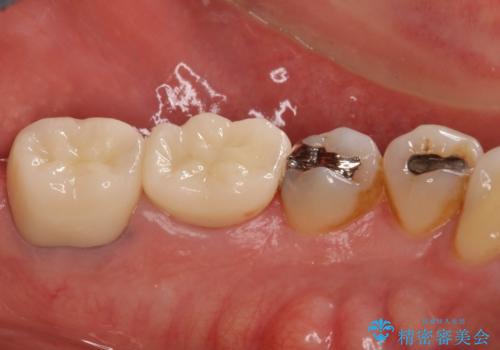

部分矯正を併用した奥歯のインプラント補綴治療

部分矯正期間中はアンカースクリューやフック、ゴムなどが粘膜にあたり、大変な思いをすることになりましたが、そのおかげでインプラント補綴した歯と最後方歯の位置が非常に良好となり、まるでご自身の歯のように咬むことができるようになりました。